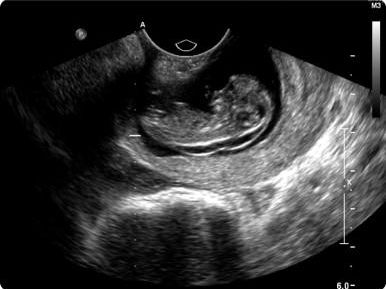

患者,女,年龄36岁,通过宫内受精而怀孕,因被检查出宫颈异位妊娠而被转至本院。当地医院在该患者妊娠6周零6天时查出异位妊娠,在其妊娠7周时给予单剂甲氨蝶呤50 mg/m2肌内注射,妊娠9周时再次给药。然而这2次治疗均未能解决异位妊娠。该患者在妊娠11周零1天时来到本院接受进一步治疗。当时,她的人绒毛膜促性腺激素(hCG)水平为26,861 IU/L。该患者否认任何阴道出血或疼痛。 结论 超声影像显示,异位妊娠位于宫颈基质后部(见图1)。值得注意的是,胎儿颈背部皱褶厚度为2.3 mm。该患者在入院当天接受了子宫动脉栓塞术;次日,在手术室对进展期异位妊娠进行根除治疗。通过阴道窥镜发现,宫颈后方有1处缺损伴胎膜脱垂(见图2)。吸出8 ml羊水,送往实验室进行细胞学分析。然后将1枚细针插入胎儿胸腔,向胎心内注射氯化钾以确保胎儿死亡。在胎儿心搏停止后将细针从胎儿体内撤出,向羊膜腔内缓慢注入甲氨蝶呤80 mg。整个手术过程在动态超声引导下进行。